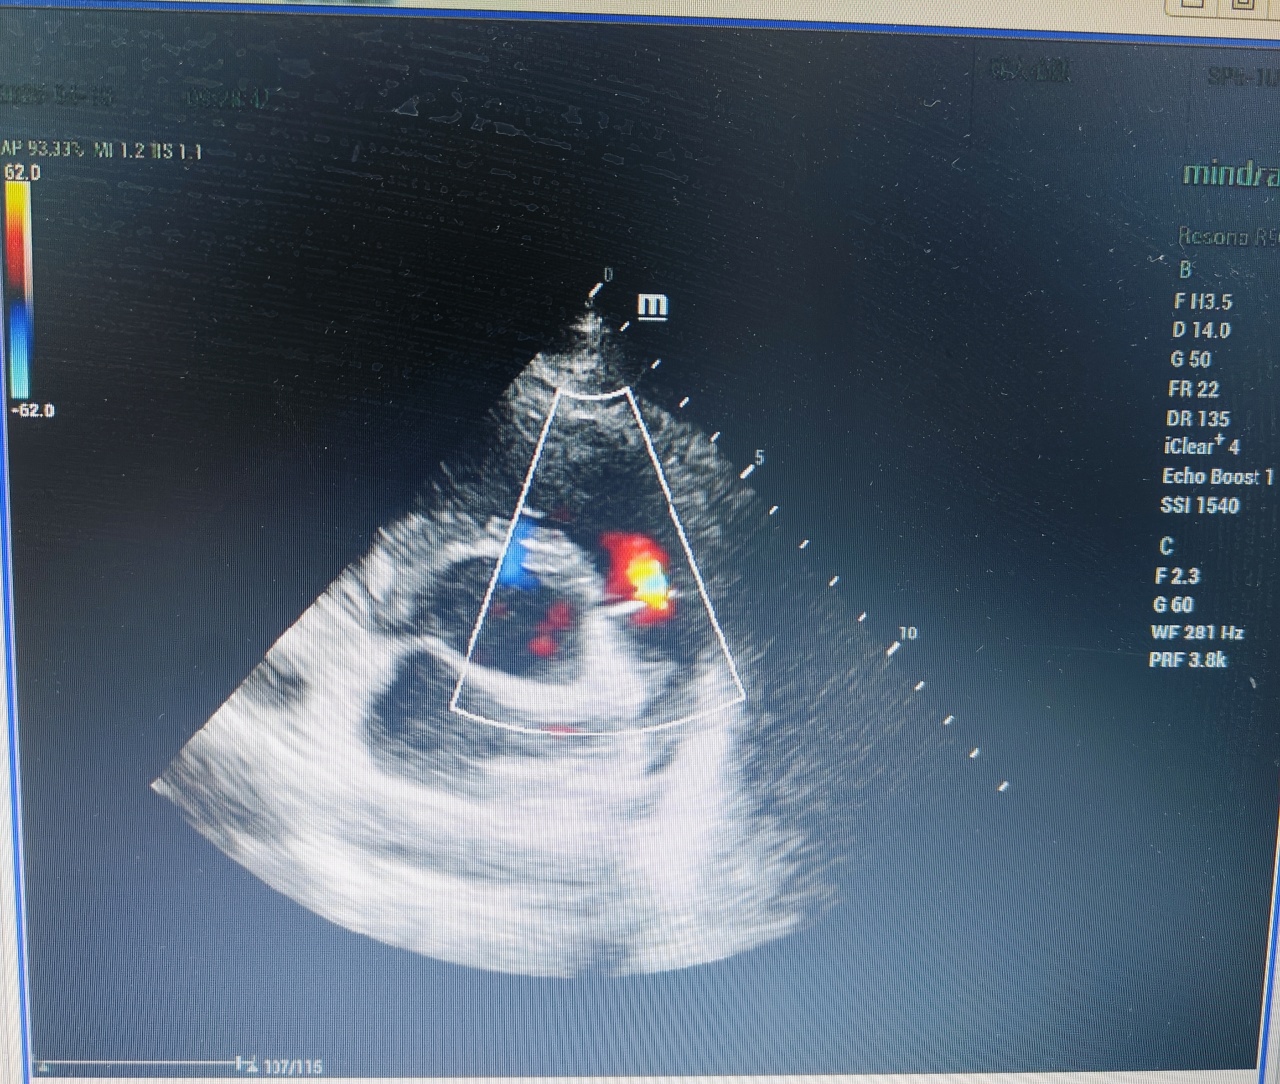

心脏超声(又称“超声心动图”)是一种利用超声波技术无创检查心脏结构和功能的影像学方法。它如同给心脏做“实时直播”,能清晰显示心脏大小、瓣膜开闭、心肌运动及血流状态,是诊断心脏病的重要工具。

1. 结构异常:如先天性心脏病(房间隔缺损、室间隔缺损)、心肌肥厚、心腔扩大等。

2. 瓣膜疾病:评估二尖瓣、主动脉瓣等是否狭窄或关闭不全。

3. 心功能评估:测量心脏射血分数(EF值),判断心力衰竭程度。